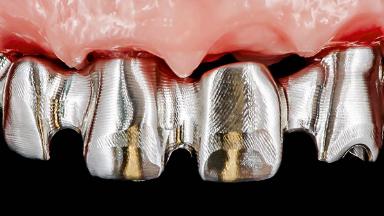

This case features the flapless computer-guided placement of 7 bone-level implants, distributed to provide maximal support for the prosthetic framework. A rigid one-piece metallic framework was utilized as an interim restoration to reduce the risk of fracture associated with this prosthetic design. As part of the clinical examination, the SAC Assessment Tool was used, resulting in a surgical and restorative risk classification as “complex”.

Loading Protocol Immediate